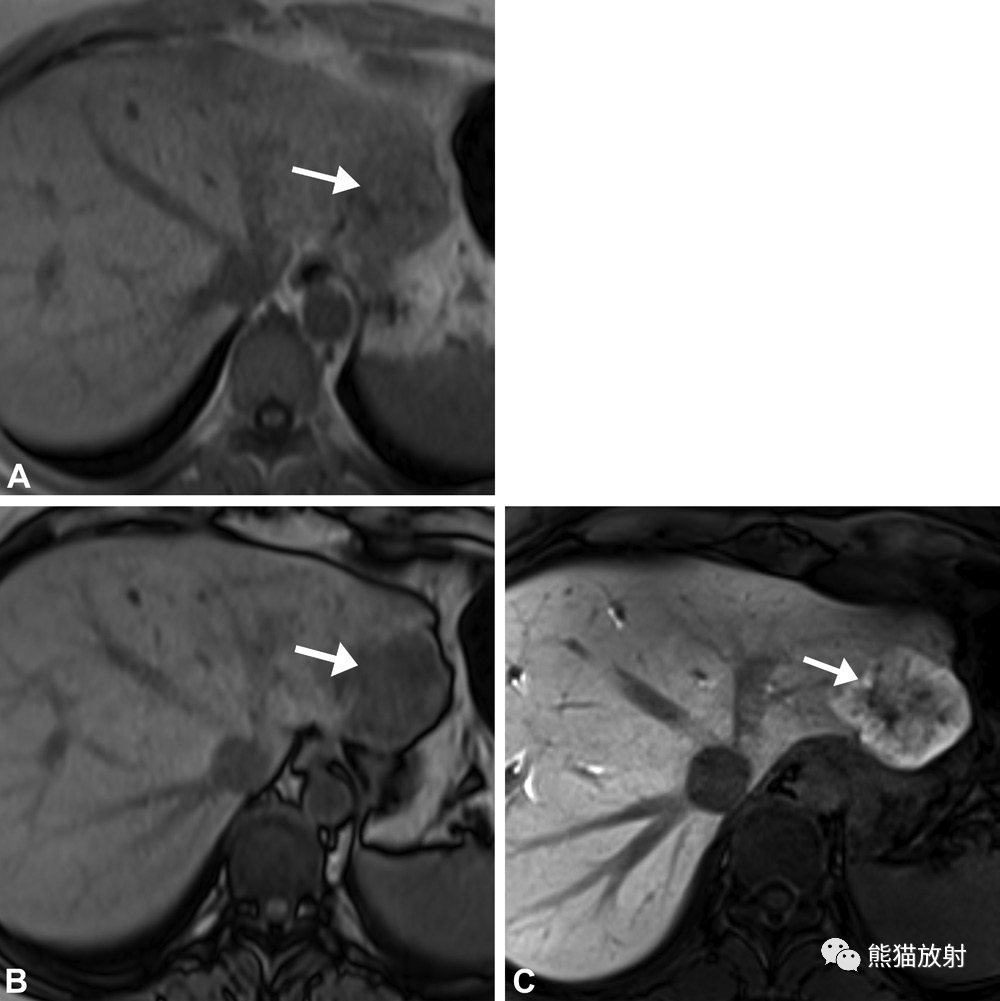

4例患者,接受基于奥沙利铂的化疗后出现新的FNH样病变。(A–C)60岁女性结肠腺癌 (A),49岁男性直肠腺癌(B),62岁男性结肠腺癌(C),治疗后肝胆期表现为低信号的FNH样病变(箭),周边环状摄取。(D)38岁男性,结肠腺癌患者,可见FNH样病变(箭),肝胆期呈均匀高信号。